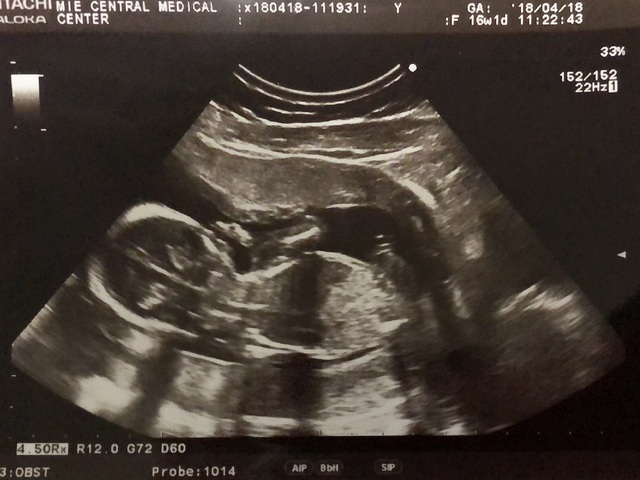

16週6日(16w6d・男の子)|keiichi さん(32歳)

エコー写真撮影時のエピソード:

待ちに待った安定期。前回の診察から間があいたのでドキドキしながらエコーに臨んだら、背骨がくっきり見えました!たまたま母と一緒に診察に行った日で、初孫のエコーに母がはしゃいでいたのを良く覚えています。帰ってから写真を見せたら、パパも大喜びしていました。